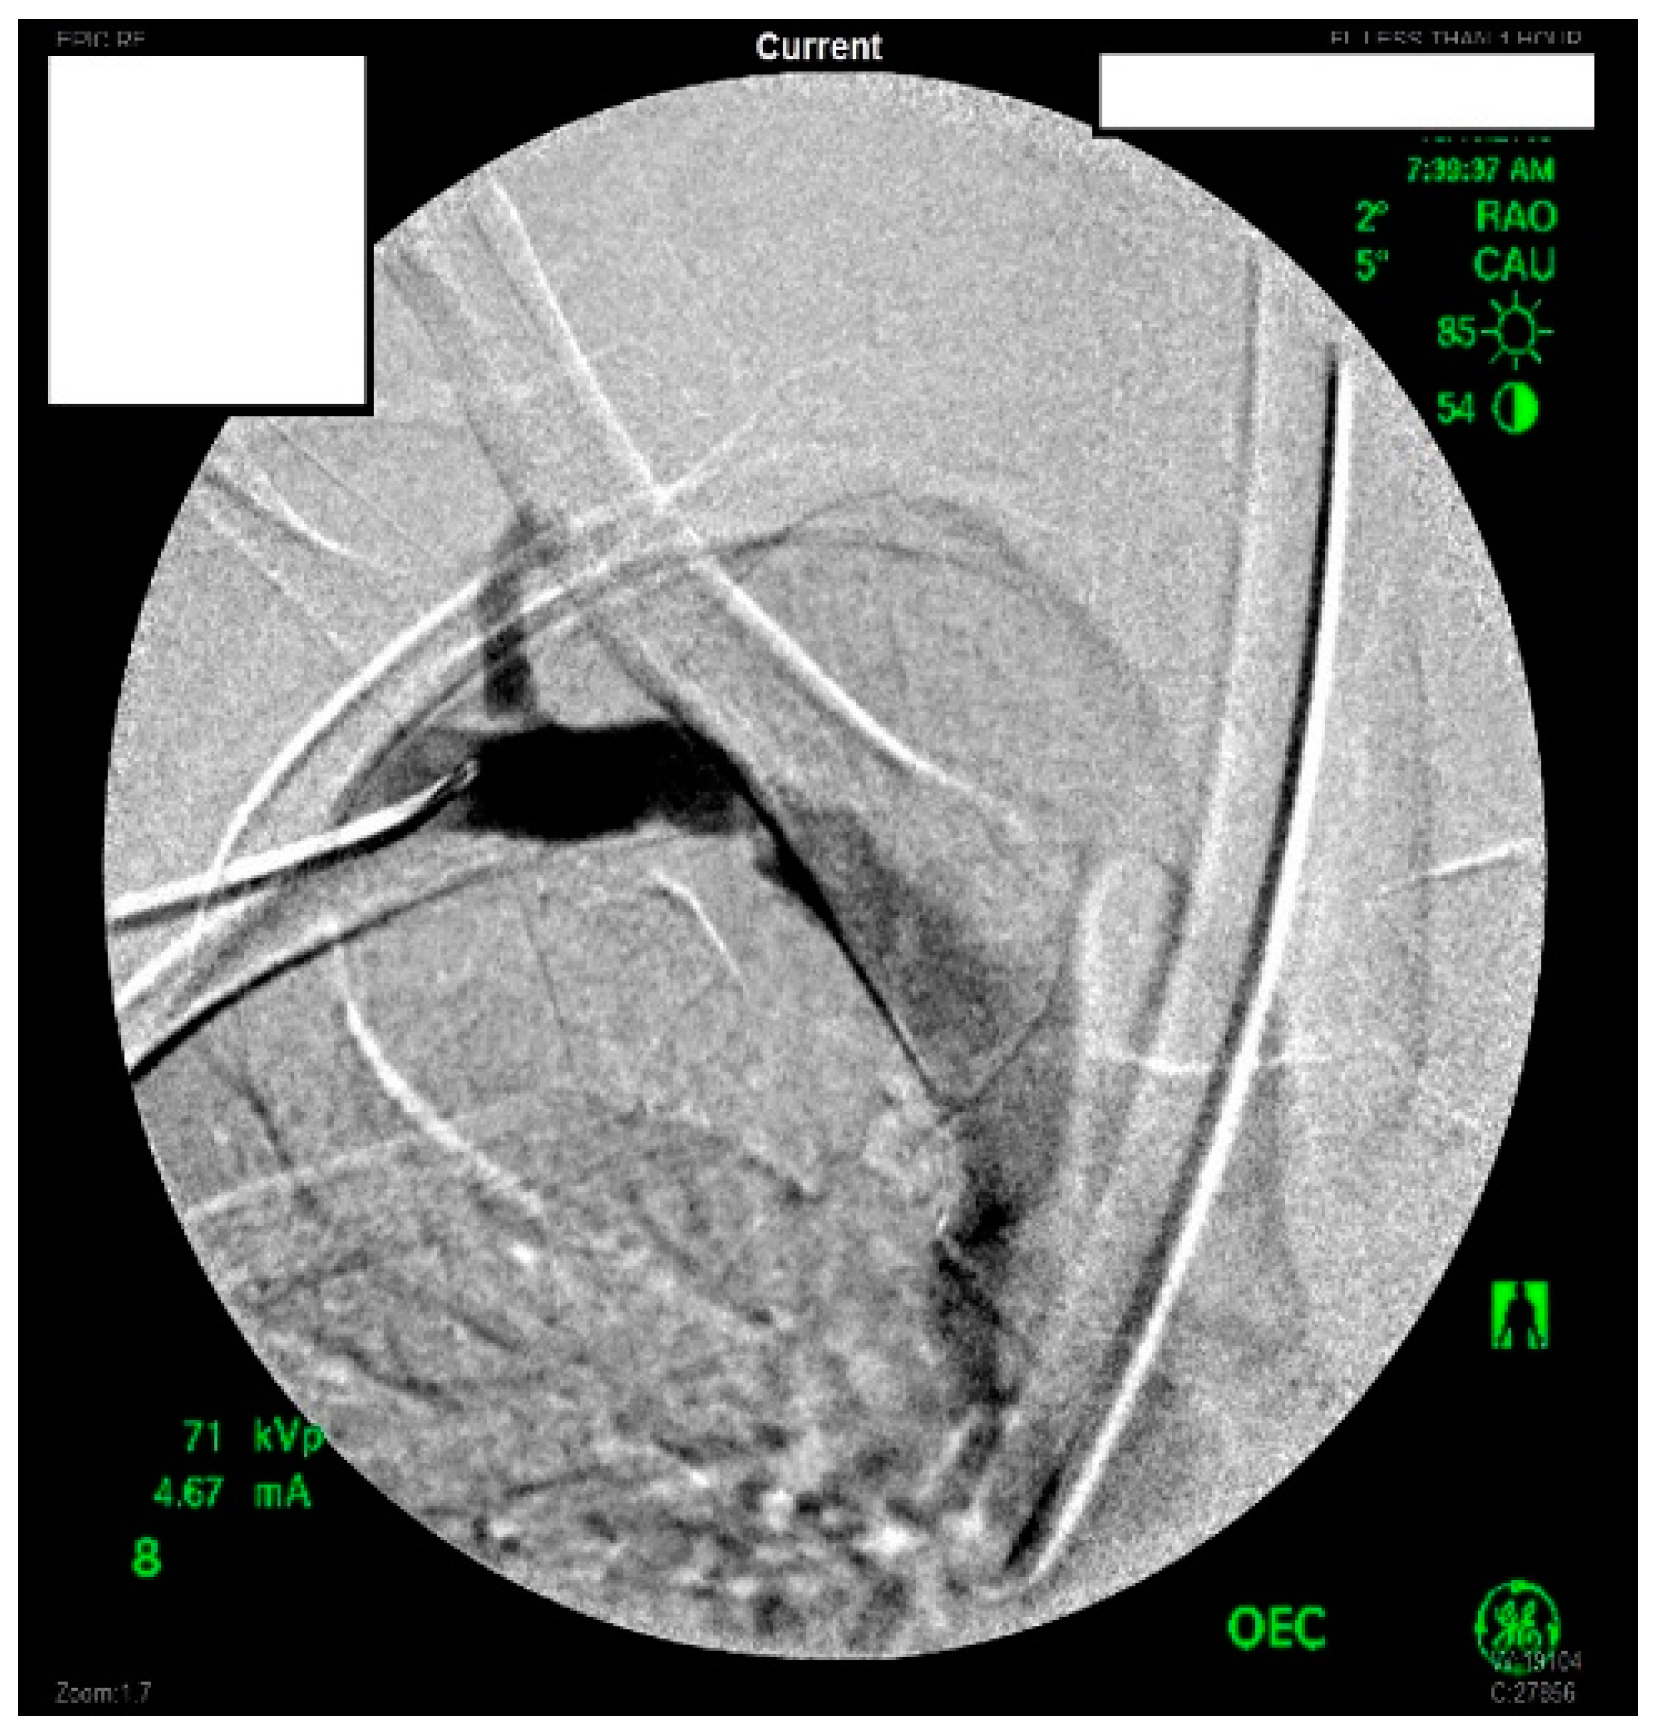

A heparin drip was then initiated, and she was taken to the catheterization lab for thrombolysis. This was carried out with Alteplase for 48 h as the patient had strong collaterals and was not in limb-threat (Figure 7, Figure 8, Figure 9, Figure 10 and Figure 11). However, her radial artery remained occluded. She was then taken to the operating room for thromboembolectomy of the left brachial and radial arteries (Figure 12). She was continued on anticoagulation post-operatively and was discharged.

Figure 7.

Left subclavian arteriography demonstrating a thrombosed brachial artery at the mid-humeral level and extensive collateralization proximally.

Figure 8.

Left subclavian arteriography in an ATOS patient in stress position demonstrating a totally occluded subclavian artery.